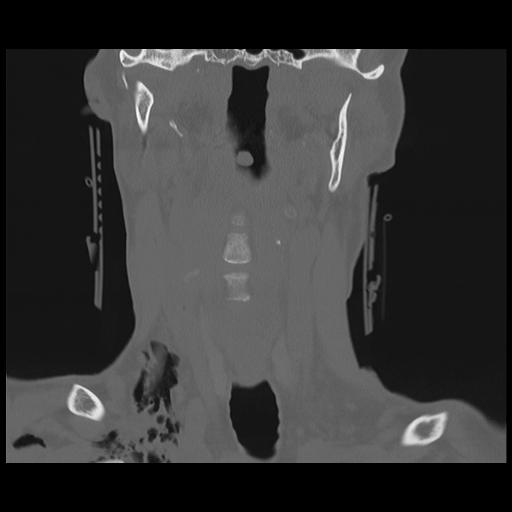

16 HUESO,,Coronal,2.000,HUESO,Coronal,